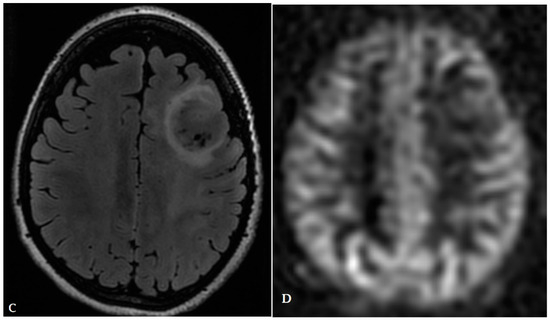

- Haldorsen, I.; Espeland, A.; Larsson, E.-M. Central Nervous System Lymphoma: Characteristic Findings on Traditional and Advanced Imaging. Am. J. Neuroradiol. 2011, 32, 984–992. [Google Scholar] [CrossRef]

- Kickingereder, P.; Wiestler, B.; Sahm, F.; Heiland, S.; Roethke, M.; Schlemmer, H.-P.; Wick, W.; Bendszus, M.; Radbruch, A.; Jalaguier-Coudray, A.; et al. Primary Central Nervous System Lymphoma and Atypical Glioblastoma: Multiparametric Differentiation by Using Diffusion-, Perfusion-, and Susceptibility-weighted MR Imaging. Radiology 2014, 272, 843–850. [Google Scholar] [CrossRef]